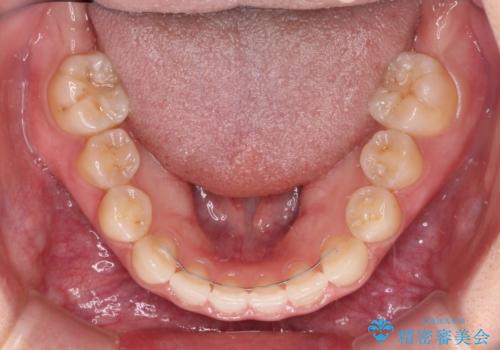

順調に後方移動することができ、わずか1年強で治療を終えることができました。

顎骨が小さいので第二大臼歯が欠損しても負担は少ないと思いますが、奥歯でもっとしっかりと咬みたいということであれば、インプラント補綴治療を4本分行うこととなります。